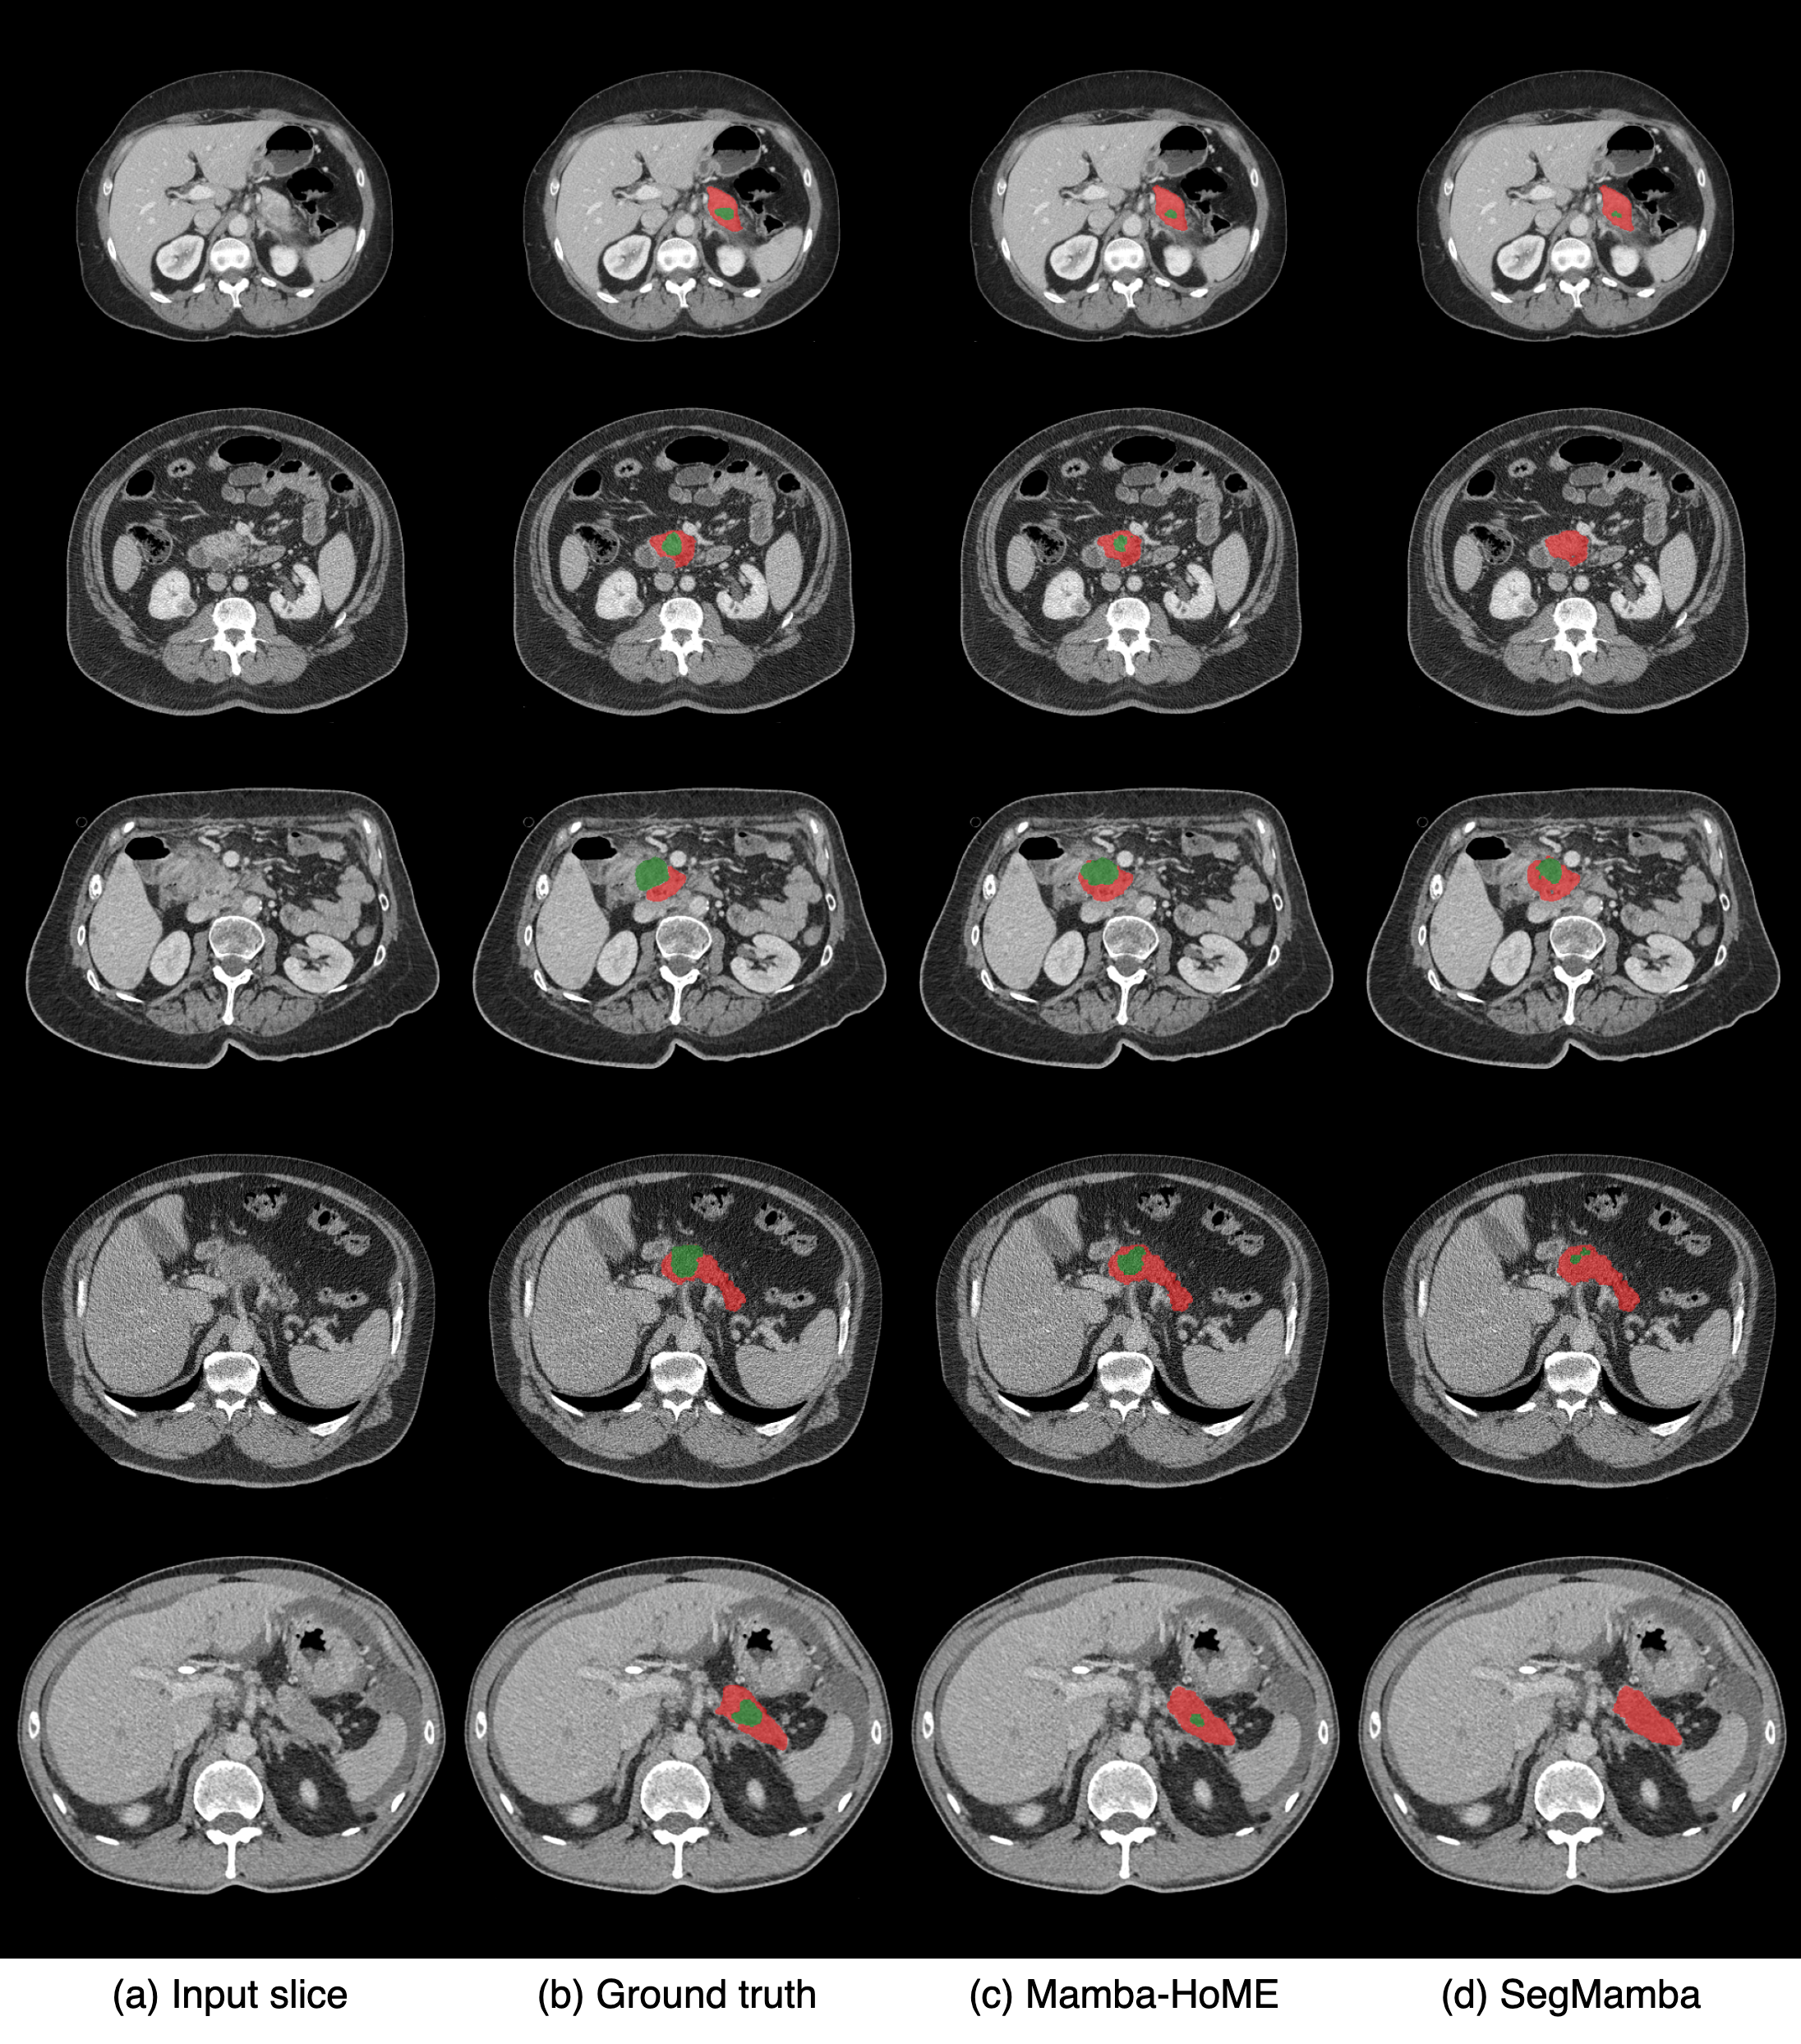

We compare our proposed Mamba-HoME with eight state-of-the-art approaches for 3D medical image segmentation, including uC 3DU-Net huang2025upping , Swin SMT plotka2024swin , VoCo-B wu2024voco , SuPreM li2024well , Hermes gao2024training , Swin UNETR tang2022self , VSmTrans liu2024vsmtrans , and SegMamba (baseline) xing2024segmamba , across four publicly available and one in-house dataset, covering diverse anatomical structures and imaging modalities, such as CT, MRI, and 3D US. Notably, both VoCo-B and SuPreM are pre-trained on large-scale CT scans using self-supervised and supervised learning approaches, respectively. Additionally, we evaluate Mamba-HoME trained from scratch against Mamba-HoME pre-trained with a supervised learning approach to assess the impact of pre-training on segmentation performance. Detailed quantitative and more qualitative results for benchmarking datasets can be found in Appendix C, and Appendix E, respectively.

Quantitative results. Results for our proposed method, Mamba-HoME, on the PANORAMA and in-house datasets are shown in Table 1. Results for other modalities, including AMOS (CT/MRI), FeTA 2022 (fetal MRI), and MVSeg (3D US), are presented in Table 2, Table 3, and Table 4, respectively.

Our proposed method, Mamba-HoME, demonstrates consistent performance improvements over state-of-the-art baselines across all benchmark datasets and three imaging modalities. Evaluated under two distinct configurations (scratch and pre-trained), Mamba-HoME achieves superior segmentation accuracy, obtaining the best results in terms of both DSC and HD95. Despite having a relatively large number of parameters (170.1M) compared to competing methods, it exhibits low GPU memory usage during inference (see Table 1), a crucial advantage for processing high-resolution 3D medical data. Although inference is approximately 30% slower than the baseline, the performance gains present a compelling trade-off between accuracy and efficiency. The Wilcoxon signed-rank test indicates a significant difference between Mamba-HoME and other state-of-the-art methods, with a significance threshold of p<0.05p<0.05.

To evaluate generalizability, we compare the proposed Mamba-HoME with several state-of-the-art networks. Specifically, we investigate four configurations on the AMOS dataset: (1) training solely on CT, (2) pre-training all models on CT and fine-tuning on MRI, (3) training solely on MRI, and (4) joint training on both CT and MRI. Table 2 shows that Mamba-HoME demonstrates superior generalizability across modalities compared to other models. Trained from scratch and further pre-trained on large-scale CT and MRI datasets, Mamba-HoME exhibits strong cross-modal generalizability to 3D ultrasound data, a modality with distinct challenges such as high noise and lower resolution. Leveraging robust, modality-agnostic feature representations, the pre-trained model adapts to 3D ultrasound via efficient fine-tuning, outperforming state-of-the-art methods in both DSC and boundary HD95 metrics, as shown in Table 4. Qualitative results in Figure 2 further illustrate its ability to handle ultrasound-specific artifacts. This cross-modal transferability highlights the model’s versatility across diverse imaging modalities. Moreover, Mamba-HoME demonstrates strong generalizability to external datasets within the same modality, especially MSD Pancreas and in-house CT dataset for PDAC and pancreas segmentation, outperforming several state-of-the-art methods in both DSC and HD95 metrics (see Table 11). Detailed results for the generalizability analysis can be found in Appendix F.